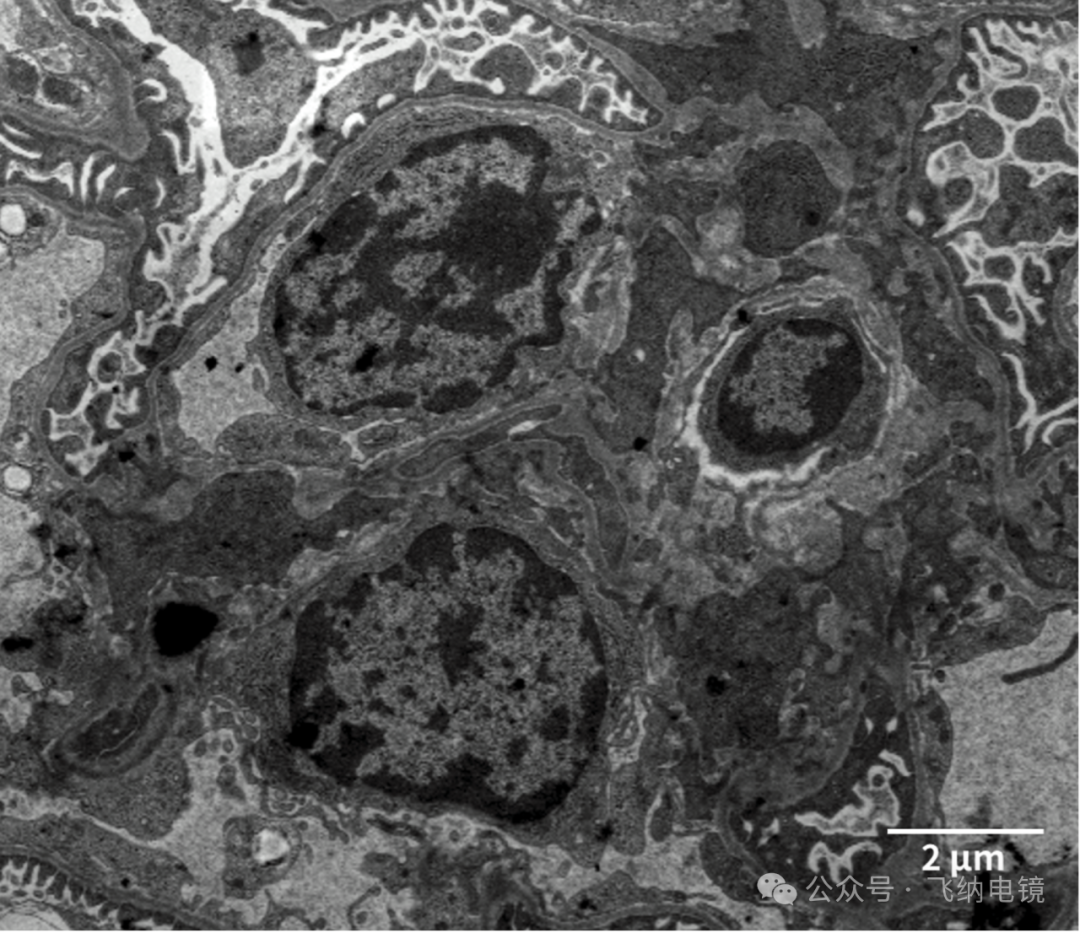

使用 Pharos STEM 台式场发射生物电镜,低倍下可见到肾小体的足细胞,基底膜,内皮细胞,系膜区:

系膜细胞(mesangial cell)是一种肾小球固有细胞,位于肾小球毛细血管袢之间,在台式场发射生物电镜可以看出,邻接内皮细胞或基底膜,形态不规则,细胞突起可深至内皮细胞和基底膜之间,或经内皮细胞之间伸入毛细血管腔内。肾小球系膜细胞具有分泌细胞基质、产生细胞因子、支撑肾小球毛细血管丛、吞噬和清除大分子物质以及类似平滑肌细胞收缩的功能。

足细胞(podocyte)附着于肾小球基膜的外侧,连同血管内皮细胞和肾小球基膜一起构成了肾小球血液滤过屏障。其呈星型多突状,胞体较大,由胞体伸出许多突起,称为足突,这些足突相互交错,在相邻足突之间形成了滤过缝隙,称为裂孔。